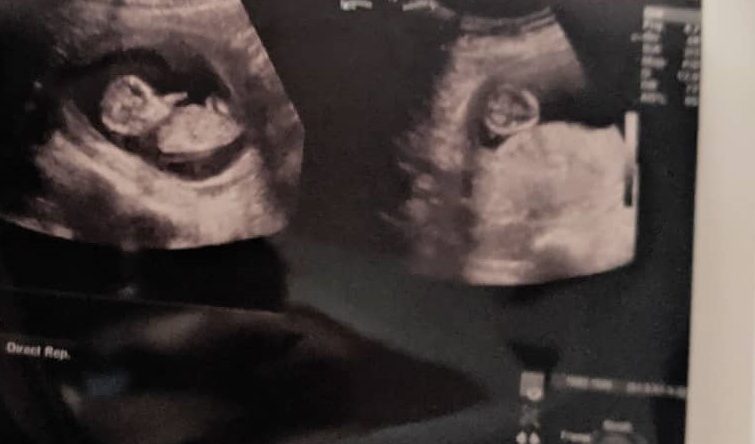

His face seemed tired and disinterested in my case. He asked me questions and told me to come over to one of the few empty beds. He ordered me to lie down and he drew the curtain to cover the area where I was and he started his exam. He shouted at the nurse to bring him something and when she did he squirted a liquid on my belly and put the machine to my belly. I was familiar with this from my monthly visits with my OBgyn. We heard the beating sound and he said “there’s the heartbeat” and he said it sounded good. He continued other examinations and proclaimed no water broke and there was no blood. He asked me specifically where the pain was. He told me that they will do an ultrasound just to make sure the baby was OK, but we had to wait because the doctor who did it was not around.

I sat down again and now I was just in so much pain I was sure I was having contractions or something. Finally someone called my name and I looked up because it was a foreign accent. I don’t know why I was surprised, but it was a tall, white doctor. He told me to follow him and as I was going off with him, I quickly explained to my partner what was going on. He led me into a small room, with a small bed and the ultrasound machine. He asked me to lay down and asked me how good my English was. I told him, I spoke very good English and he proceeded with the exam. After everything he told me that everything looked good, the baby was fine and he also asked me where the pain was and without warning he proceeded to give me a slight hand chop on the upper left side of my back and I thought I was going to die. He told me “it could be your kidney” and it kept tapping all the way down asking if I felt pain. I told him it was only painful when he hit that one spot. He said Ok and took me back to the room where I was.